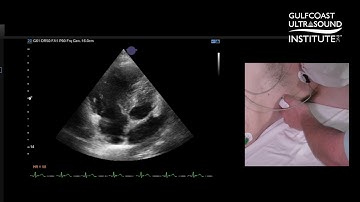

Step By Step RV Evaluation Part 2: TAPSE, TAPSV & RIMP